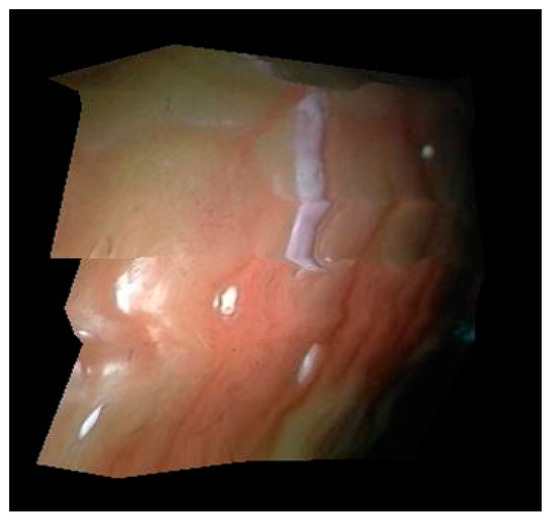

3.1. 3D Curved Surface Reconstruction Experiment

3.2. Feature Point Tracking Experiment